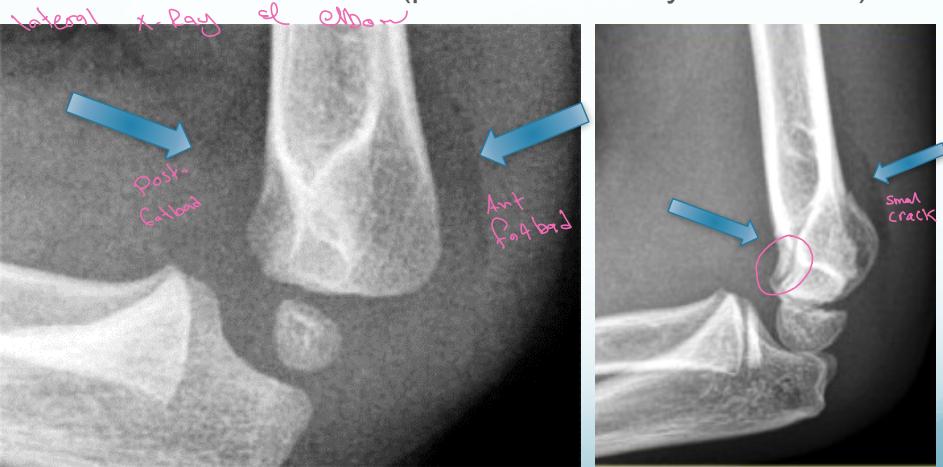

Fat Pad Sign:

- Posterior fat pad always appears in bleeding/hemoarthrosis - always abnormal

- Anterior fat pad may appear in bleeding

Important: If there’s no fracture line but there’s fat pad, treat it as minimally displaced with back slab for 2-3 days and repeat X-ray